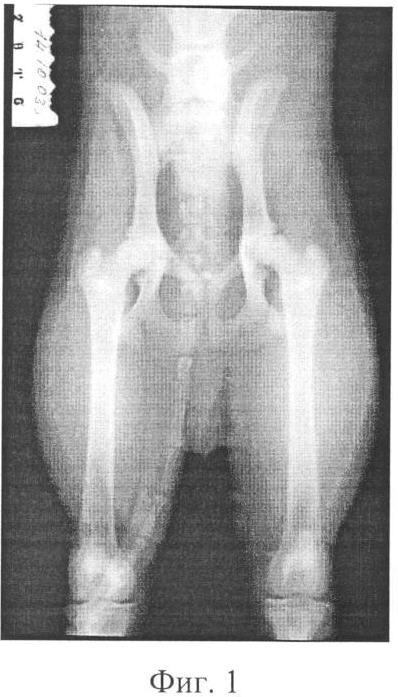

Фиг.1 – рентгенограмма тазобедренного сустава собаки до эксперимента;

Собака № 2816, возраст 7,5 месяцев (фиг.1). Для получения модели дистрофического процесса в тазобедренном суставе выполнена операция: резекция дорсального края вертлужной впадины, тенотомия связки головки бедренной кости справа.